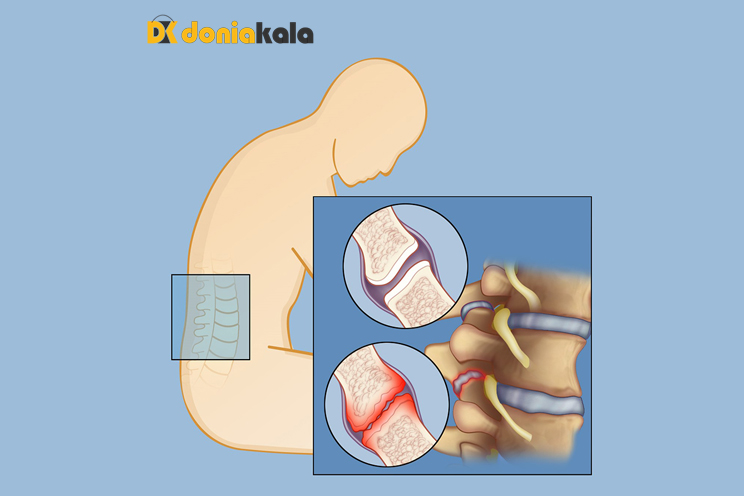

کمردرد خفیف در میان بزرگسالان نسبتاً رایج است. اما درد شدید و دائمی در پشت می تواند اتفاق بیفتد، به خصوص با افزایش سن. آرتروز فاست Facet joint arthrosis عارضهای است که ممکن است افراد مسنتر و افرادی را که آسیب یا ضربه به کمر خود متحمل شدهاند، تحت تاثیر قرار دهد.آرتروز فاست Facet joint arthrosis می تواند یک بیماری دردناک باشد و کیفیت زندگی شما را تحت تاثیر قرار دهد. اما راه هایی برای کمک به مدیریت و درمان آن وجود دارد. وجه ها مفاصلی در قسمت پشتی (خلفی) ستون فقرات شما هستند. آنها به تعادل ستون فقرات شما کمک می کنند و مطمئن می شوند که به درستی تراز شده است. وجوه در کنار مهره های ستون فقرات شما قرار دارند و در انجام برخی حرکات مانند چرخش به شما کمک می کنند. آنها برای عملکرد مناسب کمر شما ضروری هستند. به طور معمول، غضروف ها و کپسول های حاوی مایع متصل به وجه ها وجود دارد که لایه برداری و روانکاری را در برابر سایر مفاصل ستون فقرات فراهم می کند. هنگامی که این غضروف به مرور زمان از بین میرود یا آسیب میبیند، مفاصل فاست Facet joint arthrosis ممکن است به سایر استخوانها یا مفاصل ستون فقرات ساییده شوند. این می تواند باعث ناراحتی یا حتی درد شدید در پشت و سایر نواحی بدن شما شود.

آرتروز فاست Facet joint arthrosis وضعیتی است که معمولاً از بین نمی رود. ممکن است به شکلی مادام العمر با شما بماند. اما میتوانید با استفاده از روشهای درمانی موضعی یا انجام برخی روشها به مدیریت درد یا ناراحتی کمک کنید. آرتروز فاست Facet joint arthrosis یک بیماری پیشرونده است. اگر برای مدیریت آن اقدامات لازم را انجام ندهید، ممکن است بدتر شود و همچنین ممکن است عوارض دیگری ایجاد شود. داشتن یک سبک زندگی سالم و فعال می تواند به شما در مدیریت بیماری و جلوگیری از پیشرفت آن کمک کند. اگر بیماری به اندازه کافی پیشرفت کرده باشد، ممکن است برخی از عوارض رخ دهد. خارهای استخوانی هنگامی که غضروف و کپسول های پر از مایع شما در نتیجه آرتروز فاست Facet joint arthrosis فرسوده می شوند، استخوان های شما می توانند مستقیما شروع به لمس کنند. آنها می توانند به هم مالیده شوند که ممکن است بسیار دردناک باشد. این می تواند شرایطی به نام خار استخوان ایجاد کند. قسمتهای بیرونی استخوانهای شما معمولاً صاف هستند زیرا توسط غضروف محافظت میشوند. هنگامی که خار استخوانی دارید، استخوانها در مکانهایی که به هم ساییده میشوند، خشن میشوند. این به خودی خود معمولاً باعث درد نمی شود، اما اگر خار به عصب برسد می تواند دردناک باشد. بزرگ شدن مفاصل ـ مفاصل آسیب دیده شما می توانند در نتیجه آرتروز فاست Facet joint arthrosis بزرگتر شوند. این بیماری همچنین ممکن است برخی از بافت های حمایت کننده اطراف مفاصل شما ( رباط ها ) را بزرگ کند.